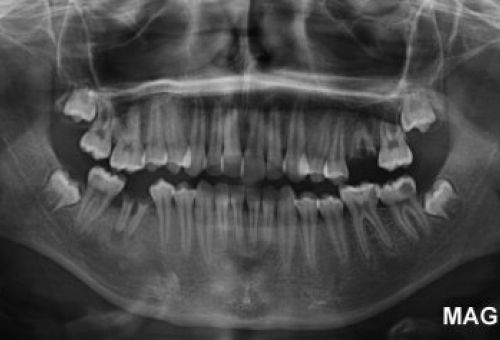

Las imágenes que se obtienen, mediante cortes y rayos X, nos permiten hacernos una idea muy clara de la situación de las piezas dentarias, sus características, su estado y las características de los tejidos blandos que las rodean.

La prueba Dentascan 3D es muy útil para prácticamente cualquier tratamiento, sobre todo en implantología, ortodoncia y reconstrucción maxilofacial.

- Cirugía dental. Es fundamental para conocer el estado de la raíz y los tejidos blandos antes de iniciar la cirugía.

- Implantología. Con esta prueba conoceremos mejor la estructura ósea del paciente y asegurar así el éxito con la colocación del implante.